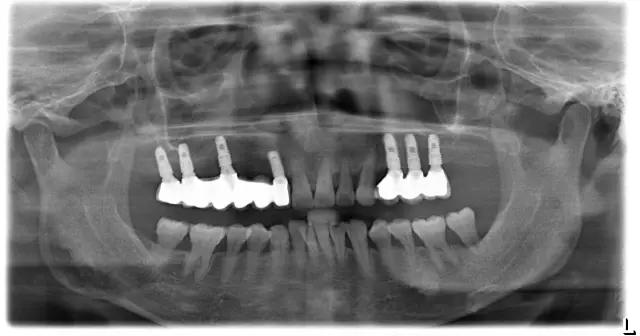

▲种植前

▲种植后